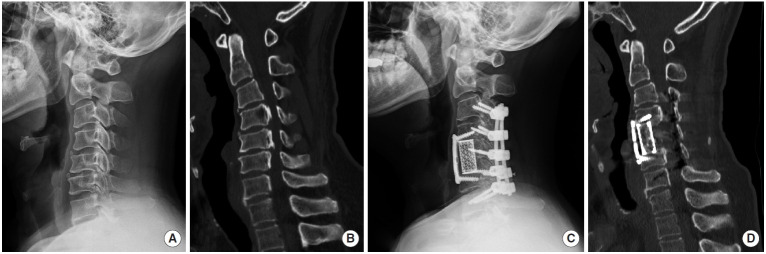

Surgical Strategy for Cervical OPLL with Kyphosis: Balancing Anterior, Posterior, and Combined Approaches - A Commentary on "Long-term Outcomes of Multilevel Anterior Cervical Osteotomy and Posterior Instrumentation for OPLL-Induced Myelopathy With Cervical Kyphosis".